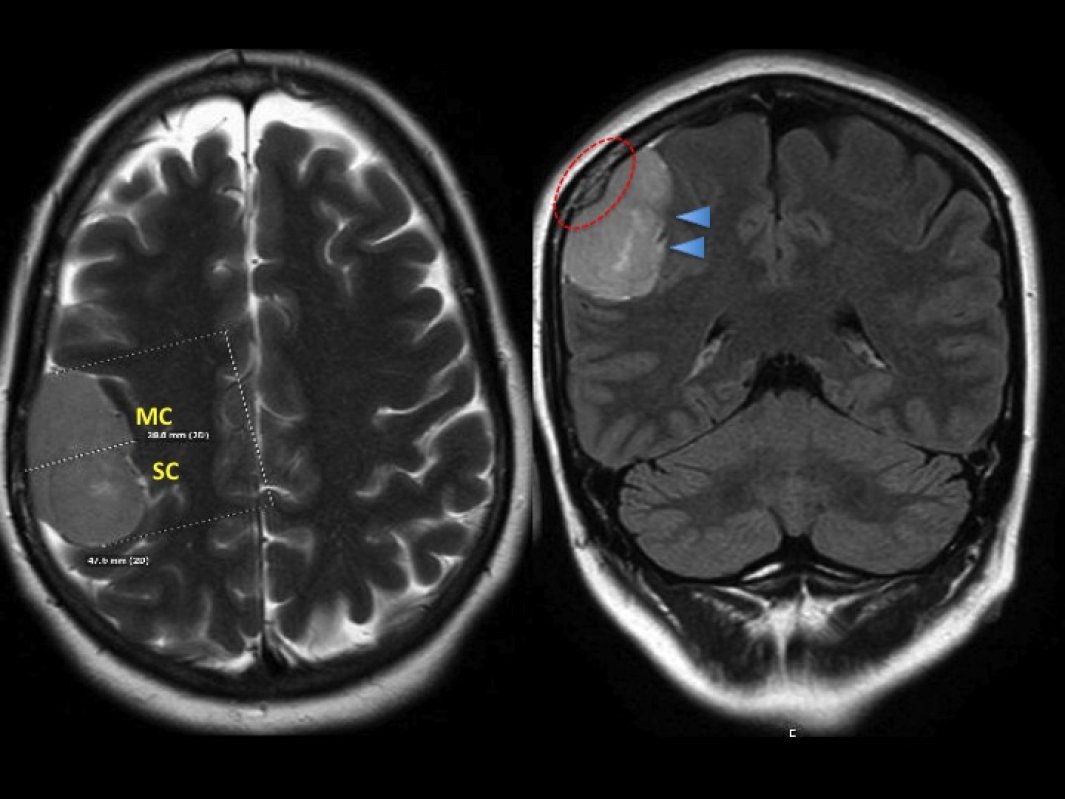

Методом вибору для діагностики менінгіоми є магнітно-резонансна томографія (МРТ) головного мозку з контрастуванням. МРТ дозволяє точно визначити межі пухлини, ступінь компресії мозкової тканини та взаємодію новоутворення з судинами або черепними нервами.

Додатково може застосовуватися комп’ютерна томографія (КТ), яка допомагає оцінити стан кісток черепа та наявність кальцифікацій у пухлині.